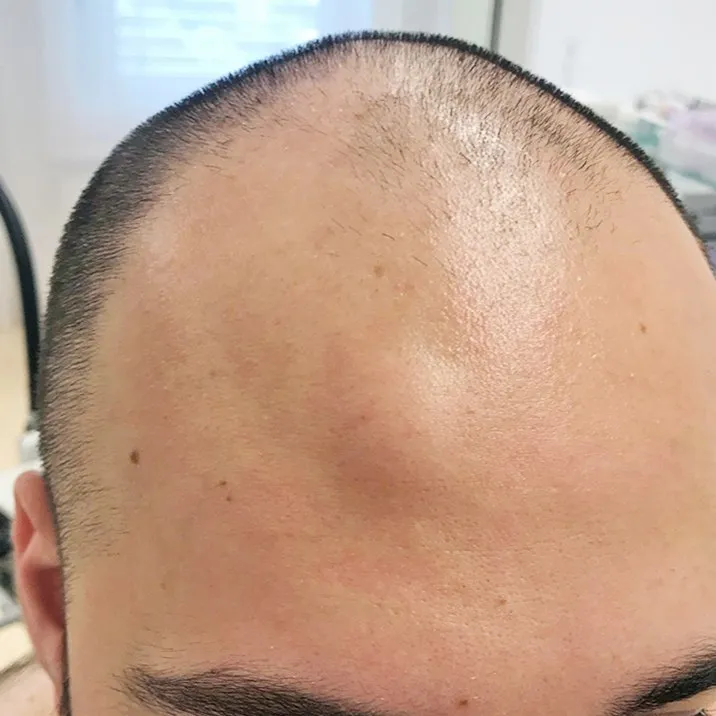

Код мкб 10 атерома головы

Код мкб 10 атерома головы 109 фото